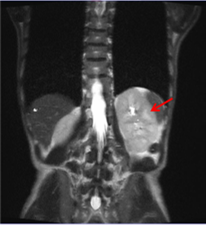

肾脏B超:左肾大小 116×54mm,右肾大小 119×50mm,双肾形态饱满,回声减低且不均匀。

肾脏MRI:双肾增大(下图:红色箭头)。